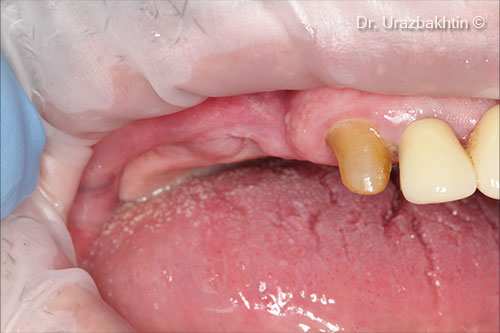

Initial intraoral view